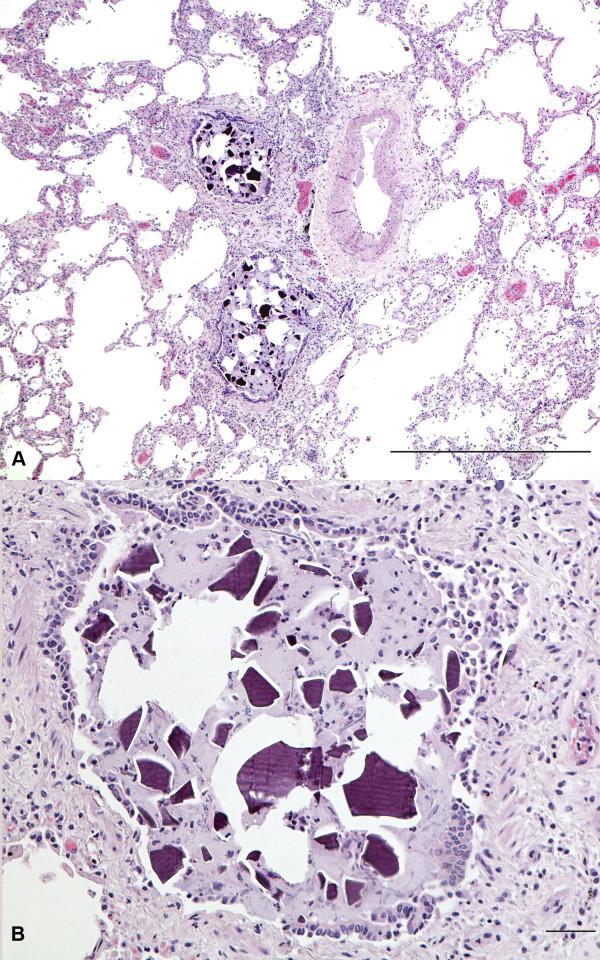

Sodium polystyrene sulfonate (Kayexalate) aspiration.

In this short report we illustrate a case of extensive sodium polystyrene sulfonate (SPS) aspiration as an immediate cause of death in a terminally ill patient. SPS is a cation exchange resin utilized to decrease potassium levels in patients with renal failure. When administered rectally in conjunction with sorbitol, colonic necrosis and perforation have been documented. On the other hand, oral administration can be complicated by aspiration, especially in very ill or debilitated patients. In our current report, histological examination of a patient who aspirated SPS shows multiple polygonal to amorphous basophilic crystalline particles deposited intraalveolarly. The purpose of our report is to familiarize pathologists with the histologic features of this rare iatrogenic complication of therapy for hyperkalemia.